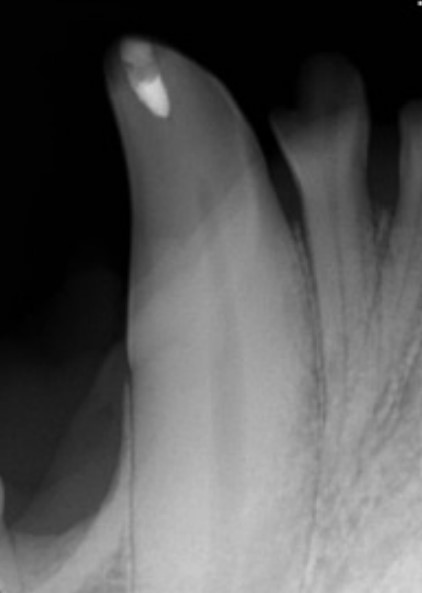

Figure 3: Canine tooth six months after vital pulp therapy. A dental bridge has formed just below the dressing material at the fracture site and the pulp canal has narrowed indicating the tooth is vital and healthy

Vital pulp therapy, also called vital pulpotomy, can be performed on fractured teeth with pulp exposure where exposure has occurred within 48 hours of treatment. In this procedure, a small amount of infected pulp is removed and a dressing powder called mineral trioxide aggregate (MTA) is placed on the pulp. The fracture site is sealed using composite--the same material used for filling cavities in humans. The dressing stimulates the tooth to form a bridge of dentin over the pulp and the tooth usually remains alive and healthy.